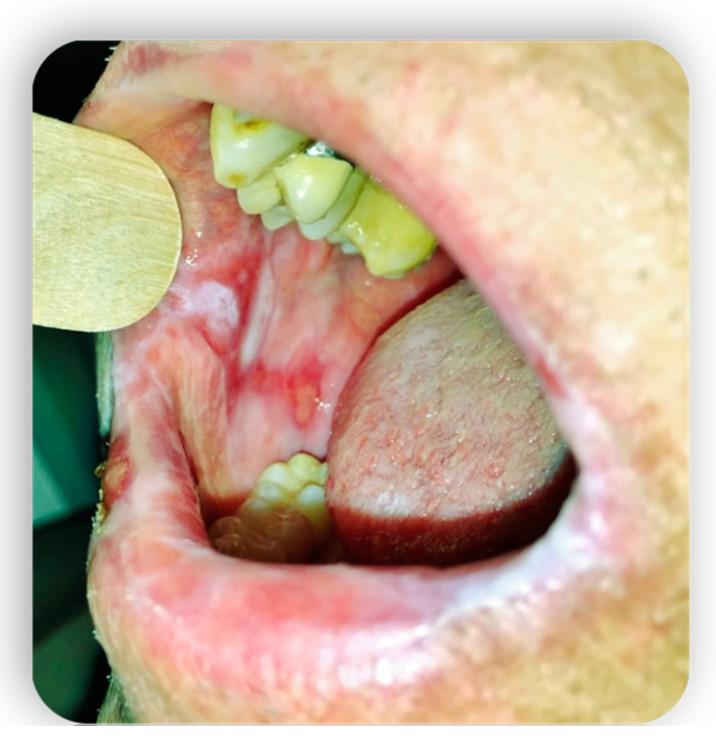

Graft-versus-host disease (GVHD) is a complication of hematopoietic stem cell transplantation (HSCT). GVHD may also develop following solid transplants or blood transfusions if white blood cells are transferred. GVHD affects multiple organs, including the oral tissues. This pictorial review provides a background of GVHD to dental practitioners, describes the most common oral manifestations of GVHD, and highlights the main treatment modifications needed to deliver dental care to patients with GVHD. A narrative review enriched with clinical data was performed by searching the scientific literature for all articles regarding GVHD and oral manifestations/therapies. All articles without exclusion criteria, except animal tests, were included in the above review. Acute GVHD may manifest in the oral mucosa; however, it often develops immediately following HSCT when routine dental treatment is postponed. Chronic GVHD may manifest in the oral mucosa, the salivary glands, and the musculoskeletal compartment. It may indirectly affect the teeth and the oral flora, putting the patient at risk for infections. Importantly, GVHD poses an increased risk for oral cancer. GVHD has a wide range of oral manifestations, some of which may affect dental treatment.